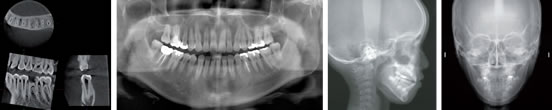

レントゲン撮影装置といたしましては、県内では初めてモリタ社製のベラビューエポックス3Dを平成23年4月1日より導入いたしました。これにより、待望のCT撮影、診断ができるようになりました。

このレントゲン撮影装置は、これ 1台でパノラマ撮影、セファロ撮影(矯正用のレントゲン撮影)、CT(3D)撮影が可能です。 最先端のデジタルテクノロジーを駆使し、より少ないX線照射線量で、高品質画像が得られる、3D画像のためのパノラマX線装置です。 さらに洗練された多彩な画像処理により、多角的な観察ができますので、より的確な診断に役立つことができます。

高感度、高解像度のフラットパネルディテクタ(FPD)による3D撮影と、CCDデジタルカセッテによるパノラマおよびセファロ撮影が可能です。

3D撮影では、φ40xH40mmからフルマウス対応のφ80xH80mmまで同じ高解像度の3D画像が得られます。